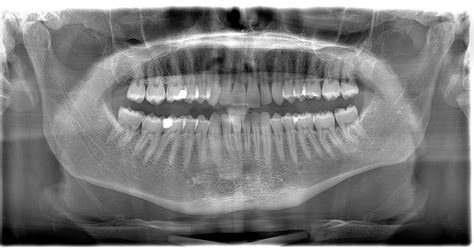

Diagnosing this condition requires more than just a physical examination of the throat. Because the root cause is structural, medical imaging is necessary to confirm the elongation of the styloid process or the calcification of the stylohyoid ligament.

• Physical Exam: The doctor may palpate the tonsillar fossa to see if it triggers the characteristic pain or a sensation of a foreign object.